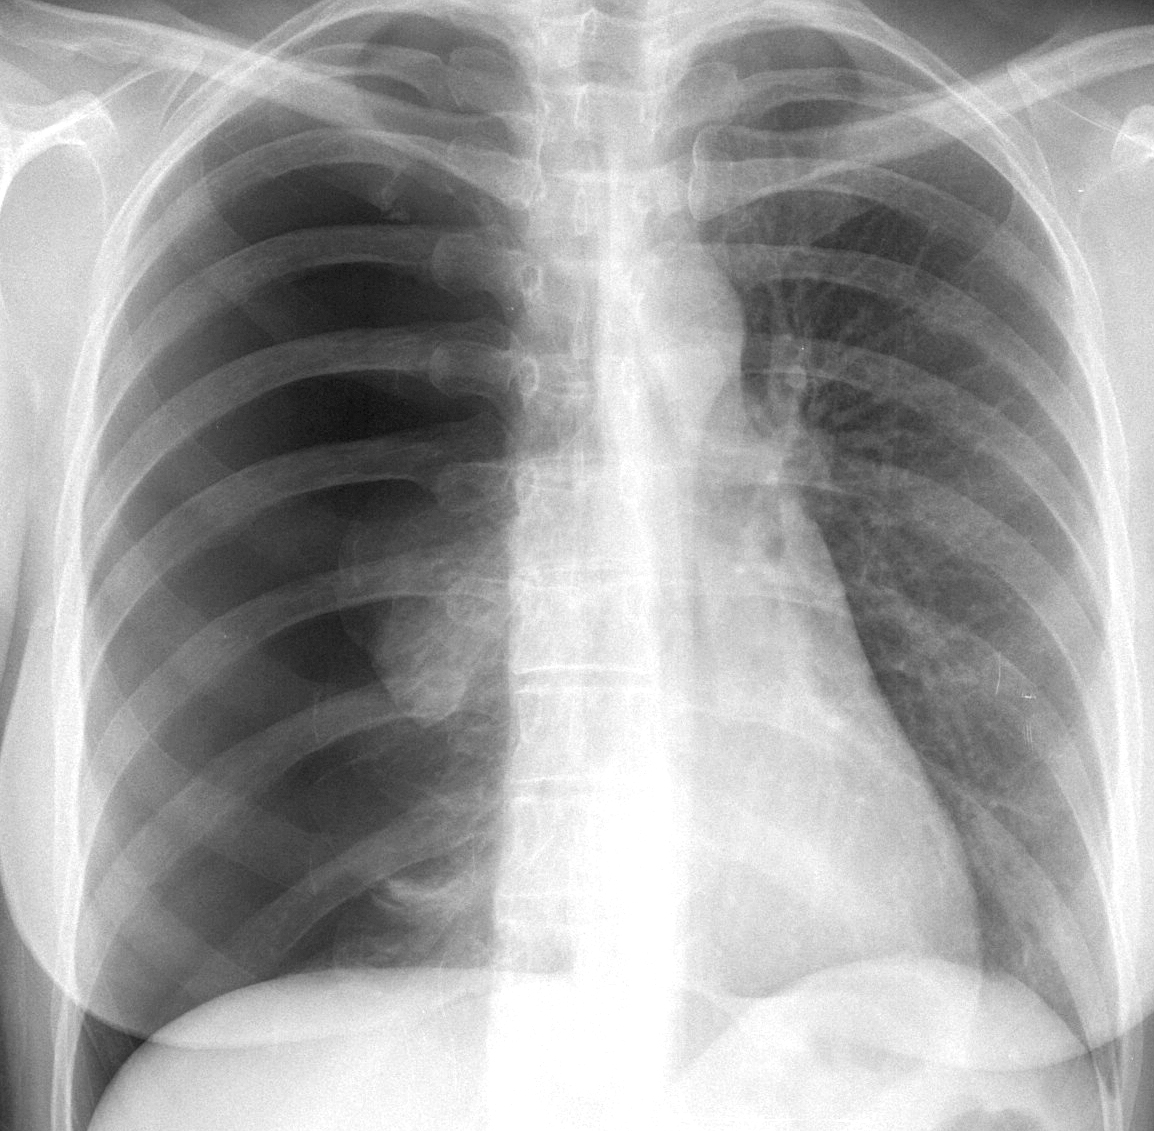

Gallery Pleural Complete pneumo (+ mild tension)

Complete pneumo

(+ mild tension)